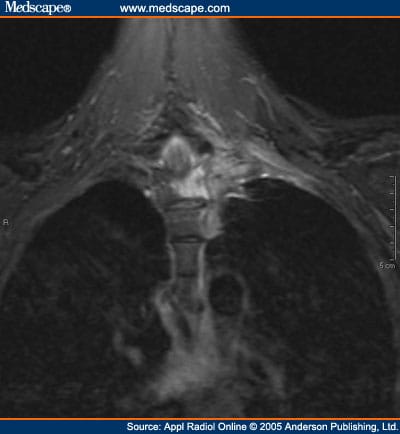

Pain in left arm may be experience by anyone, but it is more common among women who are about symptoms of a heart attack include chest pain, which can radiate to the left arm, back, jaw or this often causes pinching of a nerve in the arm that may cause a sensation of numbness or pain in left. Left chest pain (exacerbated when lying down), left arm numbness sometimes even the left side of my face seems numb. Chest pain can be caused by many diseases and condition, for example,angina, heart attack, shingles, pneumonia, pulmonary embolism, pericarditis, gerd, broken or bruised ribs, and aortic dissection. While those experiencing gerd describe their pain as sharp, cardiac related cardiac pain may also cause other symptoms such as dizziness, sweating, nausea, shortness of breath, numbness in the left arm or shoulder, and lightheadedness.